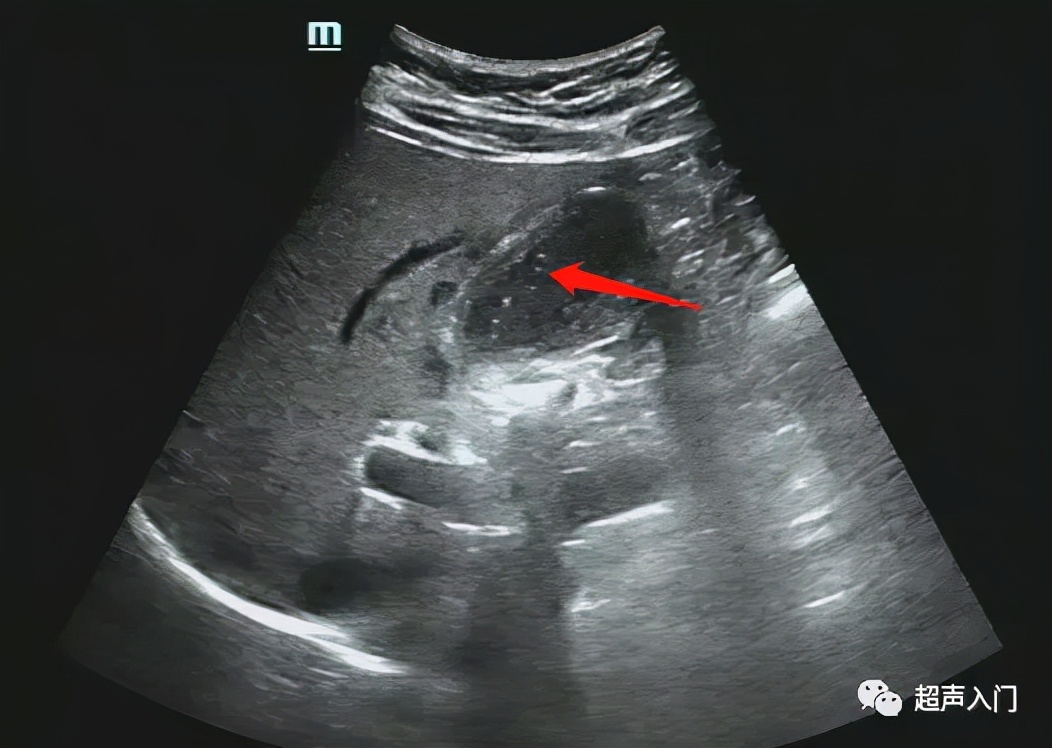

4、超声Murphy征阳性,将探头压迫胆囊体表区触痛加重,探头深压腹壁接近胆囊底部嘱病人深吸气,触痛加剧并突然屏住气不动。

5、多伴有胆囊结石,往往嵌顿于胆囊颈管部。

6、急性胆囊炎穿孔时,可显示胆囊壁的局部膨出或缺损,以及胆囊周围的限局性积液。

急性胆囊炎的诊断思路:急性起病+腹痛(可伴发热)、墨菲氏征阳性+胆囊壁增厚、水肿(双边征)。